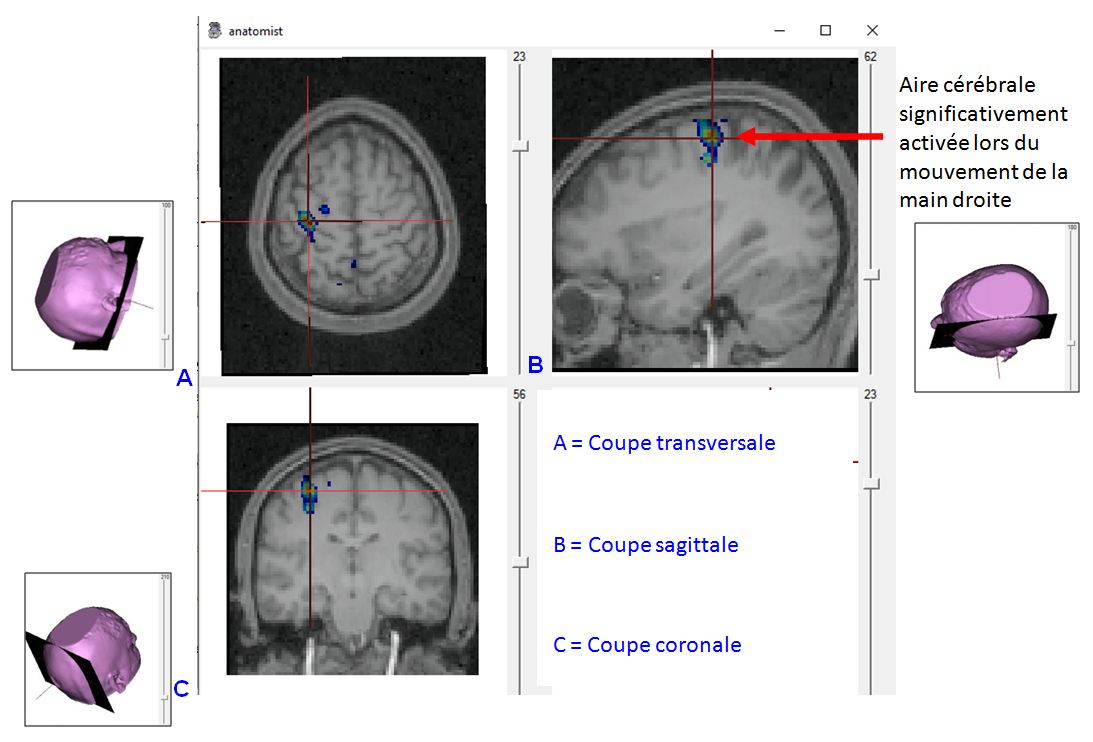

Production bouger main droite.JPG